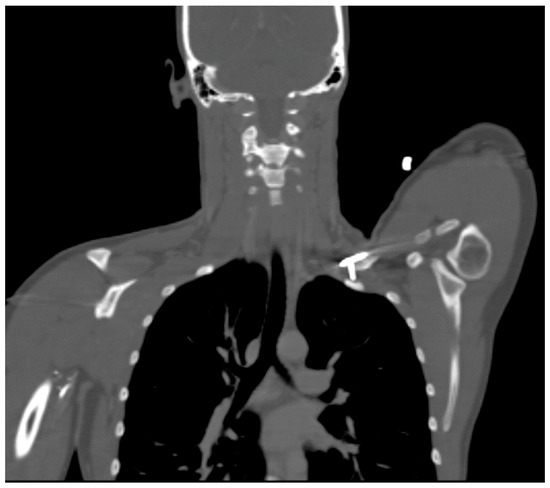

A 27 year-old female who had suffered a left clavicular fracture that was repaired previously presented with left upper extremity numbness and pain for one week. The symptoms occurred spontaneously and were intermittent throughout the week. She experienced no relief with analgesics. She presented to our Emergency Department. Brachial, ulnar and radial pulses were non-palpable. An arterial duplex revealed an occlusive thrombus of the brachial artery at the mid-humerus that appeared to be associated with the patient’s previous clavicular repair (Figure 5). A CT angiogram subsequently revealed a subclavian artery aneurysm adjacent to one of the screws from her prior clavicle repair (Figure 6).

Figure 6.

CT angiogram demonstrating a screw abutting the thoracic outlet in an ATOS patient with a subclavian artery aneurysm.